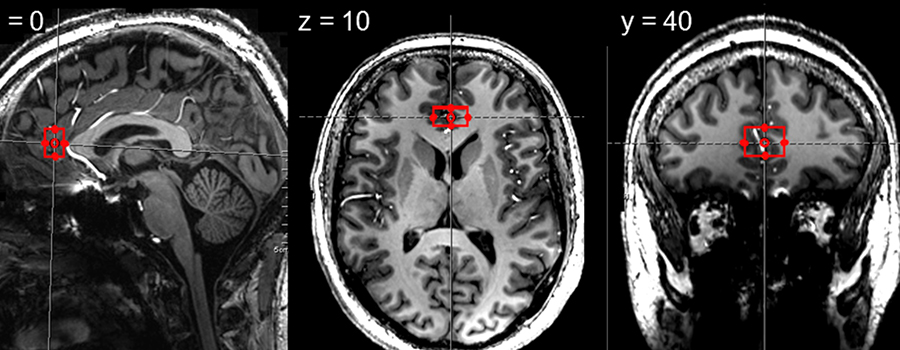

Illustration: Region called pregenual anterior cingulate cortex where we measured neurometabolites in healthy participants and in participants with major depressive disorder.

Illustration: Region called pregenual anterior cingulate cortex where we measured neurometabolites in healthy participants and in participants with major depressive disorder.